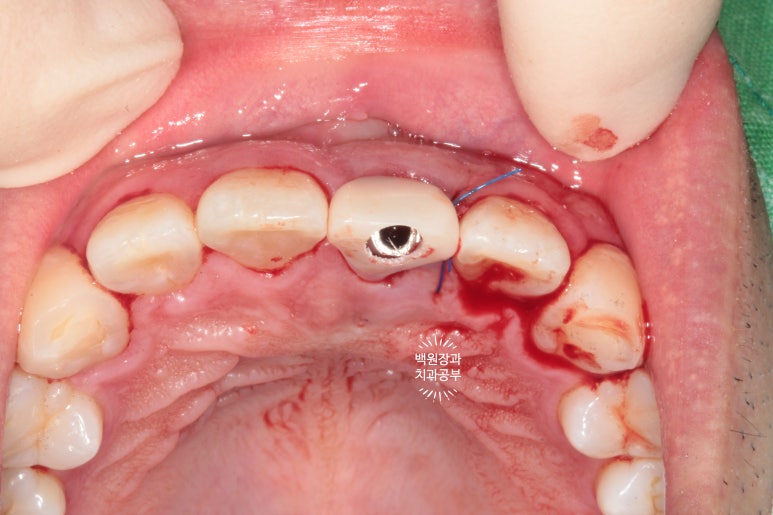

안타깝지만, 주변의 잇몸조직이 상하지 않도록, 최대한 조심히 치아뿌리 (잔존치근)를 제거하였습니다.

발치 즉시 임플란트의 핵심은 주변 조직에 위해한 영향 없이 최대한 치아뿌리만 쏙 빼내는 것입니다.!!!

제가 위에 링크 걸어드렸던, 외과적 정출술에서 사용하던 페리오톰(periotome)이라는 기구가 참 도움이 됩니다.

귀신같이 뿌리만 남아있던 앞니를 쏙 제거하는데 성공!!

보니까 뿌리는 참 건전합니다. 너무 아까웠어요..ㅠㅠㅠ 이럴 때 안타깝고 속상합니다...

이를 뽑은 자리에 조심스럽게 오스템 BA 임플란트 고정체 (fixture)을 위치시킵니다.